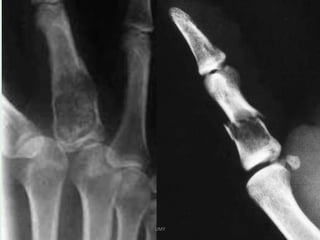

IMAGING

• X-ray & CT

Typically enchondromas are small 1 - 2cm lytic lesions with

non-aggressive features.

narrow zone of transition

sharply defined scalloped margins : may have mild

endosteal scalloping

expansion of the overlying cortex may be present but there

should not be cortical breakthrough unless fractured

Chondroid calcifications may be present : rings and arcs

calcification-STIPPLED/PUNCTATE/POPCORN

no periosteal rxn.

• The majority of enchondromas more frequently arise in

the metaphyseal region,.

A cartilaginous lesion in an epiphysis is more likely to be a

chondrosarcoma .